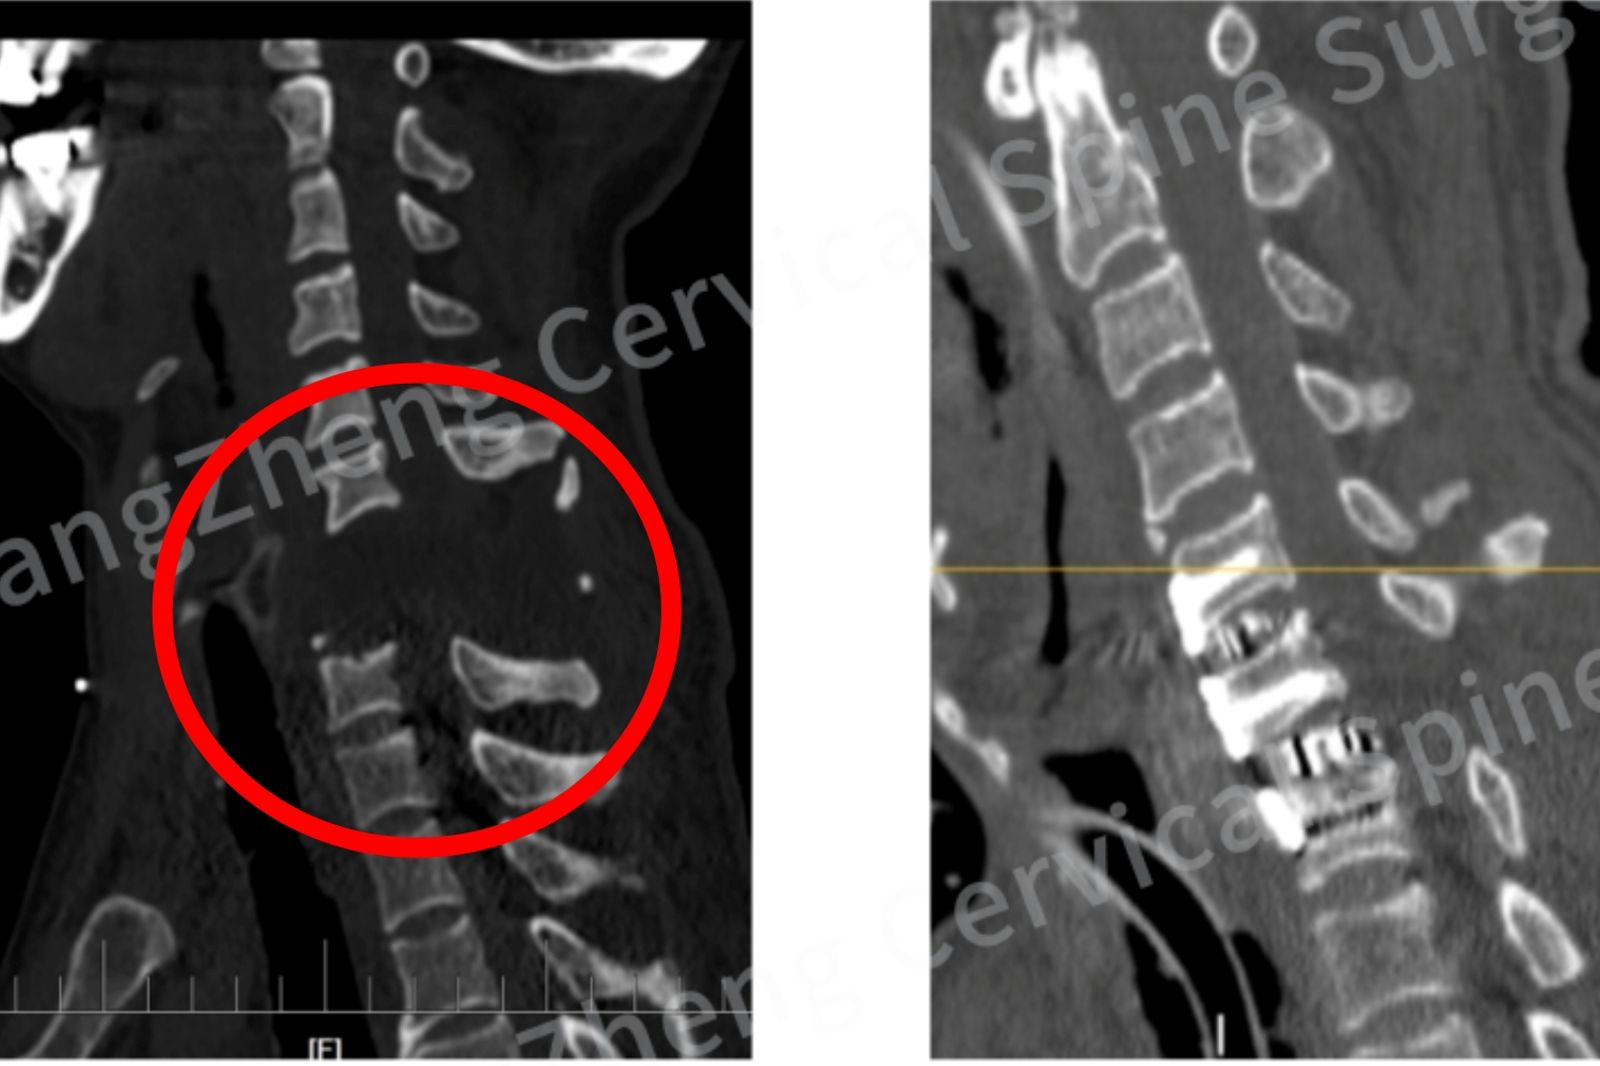

報導指出,醫生們使用了一個固定技術叫「衛星鋼板」,在一般的固定之外增加了一塊鋼板,幫助傷者的頸椎更穩定,這也是此類極端傷者中的首創。陳華江說,雖然進行手術的醫生整體思路清晰,但畢竟完全沒有先例可以參考,都是邊手術邊即時下判斷。